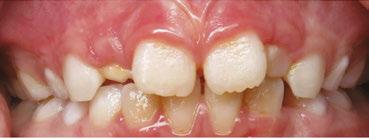

Dx: SRDB-Malocclusion Co-morbidity: Pre-WW II Physician-Dentist Collaboration

There are numerous pre-WW II papers published within the corpus of medical and dental literature that support the practice of physicians and dentists collaboratively diagnosing and treating SDB and malocclusion co-morbidity, mostly skeletal-dental maxillary transverse deficiency and mandibular distal occlusion (retrusion/retrognathia) through the ‘spreading of the deciduous arches’ during the early childhood years (30 months-7 y.o./complete primary-early mixed dentitions).2,8 These interventions had been carried out for the primary purpose of improving nasal breathing and quality of life rather than solely for the purpose of correcting so-called ‘irregularities of the teeth’. As these historically important journal articles pre-dated the 1948 initial published report of an RCT by several decades, it is unreasonable to criticize their usefulness compared to current RCT standards. Developing malocclusions are nearly always first detectable in the primary dentition (ages 2.5-7 yrs),9,10 nearly always become more complex (i.e., get worse) with age without appropriate intervention,9 and are very frequently co-morbid with pediatric sleep related breathing disorders (SRBD). In the single-digit growth

years they are non-surgically correctible with validated orthodontic/dentofacial orthopedic interventions. It seems reasonable to suggest that failure to diagnose and appropriately treat or refer afflicted young children is a medically-indefensible position.

In a lecture held in 2018 at Boston University entitled ‘Sleep Disordered Breathing/Obstructive Sleep Apnea Symposium’,21 a new screening tool called C.H.I.C.A.G.O. H.E.A.R.T.S. (C.H.) had been introduced as potentially becoming the first validated screening device specifically designed to identify CFRC physical traits that can often be comorbid with SRBD. Several of these traits are listed within the C.H. acronym (Fig. 2). For instance, under the first letter ‘C’ are listed: Crossbite 22,23 Fig. 3 and Crowded Pharynx;24,25 ‘H’: Hyper-divergent growth (Fig. 4),16 Hypertrophic tonsils and/or adenoids;26,27 ‘I’: Incompetent lips;28 ‘C’: Constricted arches (Fig. 5);23,29,30 ‘A’: Airway anatomy (Fig. 6);22,31 ‘G’: Grinding teeth (bruxism)32 and Gonial angle excess;33 ‘O’: Overweight child34 and Obtuse nose-lip angle( NLA);35 ‘H’: Highly-vaulted palate;36 ‘E’: Ezcema-atopia37 and Eye appearance-venous pooling38 and scleral show;39 ‘A’: Anterior open-bite

(Fig. 8):40 ‘R’: Retrognathia (Fig. 9) (mandible16 and/or maxilla);41 ‘T’: Tongue posture,42 tie (tether),43,44 scalloping;45 ‘S’: Septal deviation46 and night Sweats (diaphoresis).47